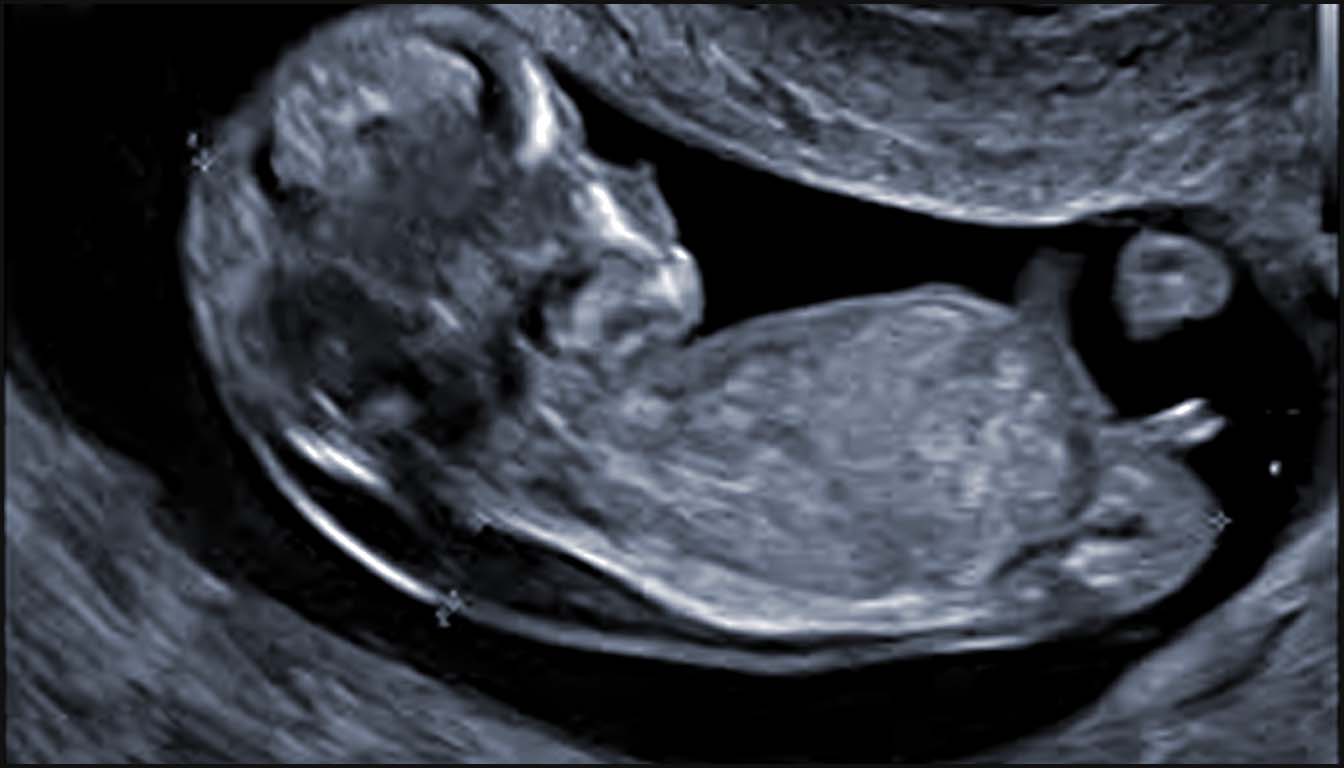

L’échocardiographie fœtale, réalisée idéalement entre 18 et 22 semaines de gestation, est l’outil de référence. Elle repose sur une analyse segmentaire séquentielle de l’anatomie cardiaque.

L’utilisation du Doppler couleur et pulsé est indispensable pour évaluer la fonction valvulaire et les flux vasculaires. L’imagerie avancée, telle que l’IRM cardiaque fœtale ou la magnétocardiographie (fMCG), peut compléter le diagnostic, notamment pour les anomalies des gros vaisseaux ou les arythmies complexes. Un diagnostic précoce dès 11-14 semaines est possible par voie transabdominale ou transvaginale pour les grossesses à haut risque.

Bien que l’échocardiographie fœtale traditionnelle se déroule entre 18 et 24 semaines, la détection précoce est désormais possible grâce aux progrès de la résolution d’image et à l’utilisation systématique du Doppler couleur et pulsé. Cette approche permet de détecter plus de la moitié des anomalies cardiaques majeures dès la fin du premier trimestre, offrant ainsi un délai supplémentaire pour les tests génétiques et le conseil parental.